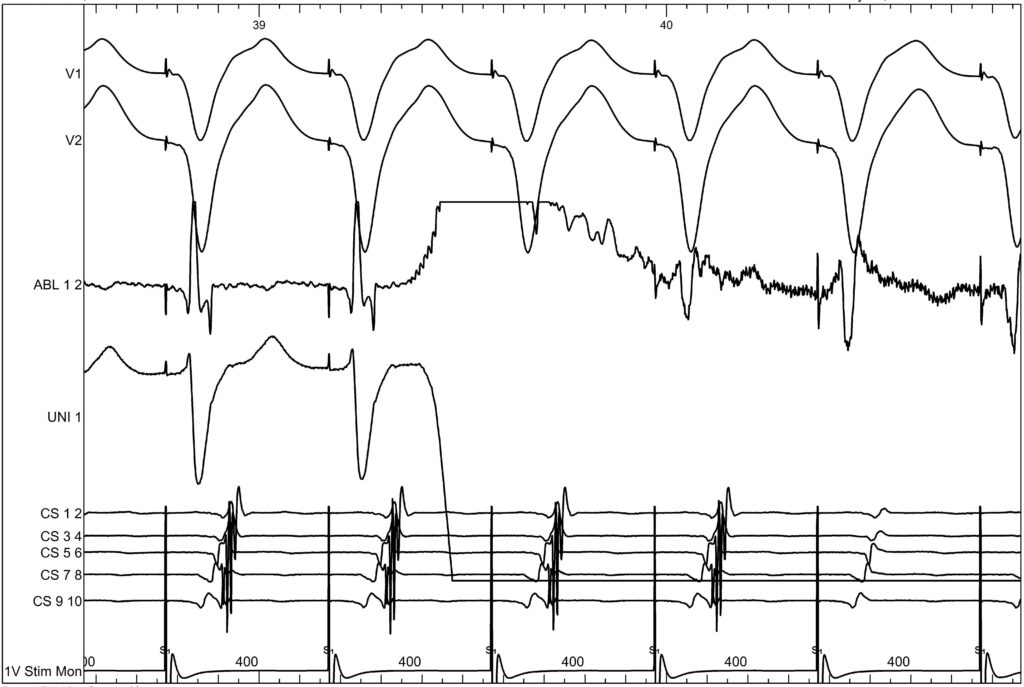

To ablate this concealed accessory pathway, ventricular pacing was performed. The His bundle was first identified, after which VA fusion was sought. Ablation was delivered at the posteroseptal region, resulting in disappearance of accessory pathway conduction within the first three seconds of energy delivery.